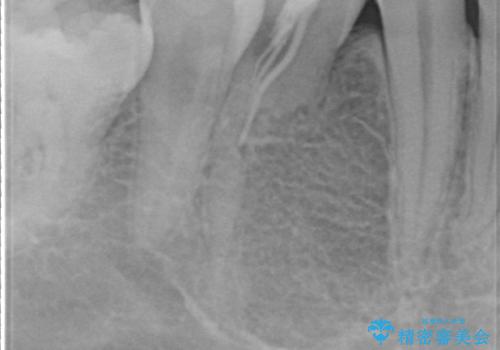

レントゲンを撮影したところ、右下4は神経のない歯で、外部吸収といって、根がだんだん短くなり、やがて抜けてしまう症状になっていました。また、アンキローシスを起こしている可能性があるため、動かない可能性が高い状態でした。